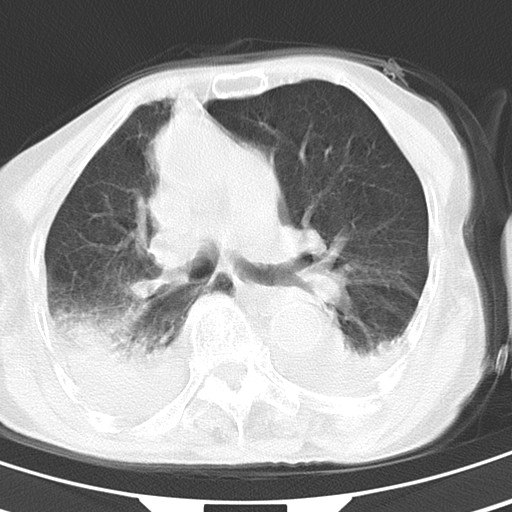

女,93岁,摔伤后检查。

右肺炎症,心功能不全伴双侧胸腔积液,右下肺膨胀不全,食管裂孔疝,冠脉钙化,心包少量积液,左侧肋骨骨折,请上传骨窗.

右侧锁骨\\肩胛骨骨折、右侧湿肺,心功能不全伴双侧胸腔积液,右下肺膨胀不全,左膈破裂或食管裂孔疝,冠脉钙化,心包少量积液,请上传骨窗.

右肺炎症,心功能不全伴双侧胸腔积液,右下肺膨胀不全,食管裂孔疝,冠脉钙化,心包少量积液,左侧肋骨骨折,右肩甲骨粉碎性骨折。93岁,高寿哇!

右肺炎症,心功能不全伴双侧胸腔积液,右下肺膨胀不全,食管裂孔疝,冠脉钙化,心包少量积液,左侧肋骨骨折,右肩甲骨粉碎性骨折。